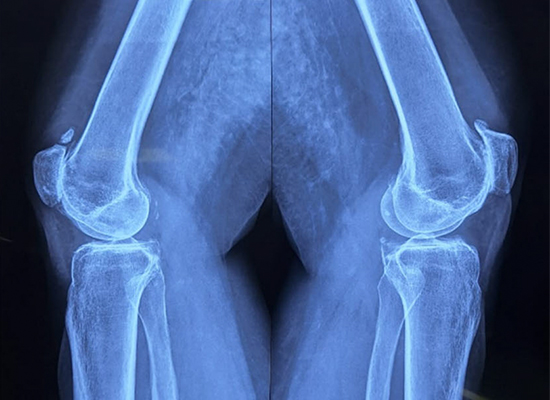

Preoperative Imaging

1

AP view showing severe joint space narrowing